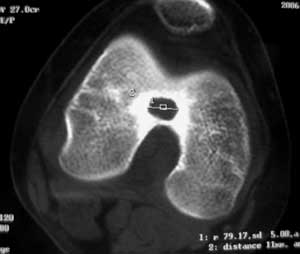

14岁女孩,7月前右膝关节疼痛,进行性加重,无外伤,无潮热盗汗,无高热,未治疗。1周前入院,下肢皮肤牵引,抗炎治疗,症状减轻。入院查右膝关节轻肿,浮膑(-),碱性磷酸酶140,余(—)。如何诊治?1周前ct 见关节面破裂,关节腔穿刺少量血性液:细胞学检查示滑膜炎改变,培养未见细菌生长。 7月前ct

6月前mri,1周前ct

病变特点:股骨的非负重区的破坏病灶,是结核的特点,病灶边沿的硬化又是细菌性感染的特点,建议检查一下肺部有无结核。

考虑结核可能性大,骨样骨瘤待排;结核单关节病变好发于承重关节,髋关节、膝关节病变占80%左右,关节局部疼痛、肿胀,活动受限,起病缓慢。骨样骨瘤多发生在长骨的骨皮质,很少部分发生在骨松质,以股骨、胫骨最常见,病灶周围有显著的反应性硬化环,局部疼痛,夜间较重,近关节的病灶有关节积液。本病例应进一步做其他检查。

低毒感染,骨样骨瘤待排,mri表现整个骨够信号异常并跨够线,良性肿瘤基本排除,(但骨样骨瘤与骨母与感染有关),病灶周边硬化不是tb表现。

病变骨质增生硬化,不支持结核。mri示病变中心内短t1、长t2信号,考虑为骨样骨瘤并瘤巢内出血。

病变特点:股骨的非负重区的破坏病灶,病灶边沿的硬化明显,ct mri均显示病变为慢性过程,关节积液不明显,考虑低毒感染可能性大,请继续抗炎治疗,不除外骨样骨瘤

病变特点:病灶较小,周围硬化环厚/明显,中心ct呈透光区,mr可见液性成分;14岁小孩,骺端关节面的病变,可考虑的病变有:1/低毒力感染,嗜酸性肉呀肿,2/软骨母细胞瘤,年龄/好发部位/信号/密度均可符合诊断,唯一不支持的是病灶中心未见点状钙化或骨化影3/腱鞘囊肿4/巨细胞瘤和骨囊肿可以不考虑。

骨骺轻度水肿,近髁间凹关节面侧骨局灶性破坏,病灶边缘有较多的环形硬化,骨显著硬化是细菌性感染的特点,关节积液不明显...抗炎治疗症状减轻,考虑为低毒感染可能性大(brodie骨脓肿可能).请继续抗炎治疗